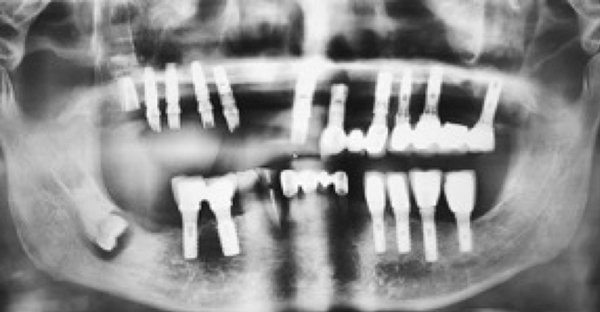

This is known as sinusitis. The answer is a clear NO. Upper jaw dental implants can protrude into the sinus cavities causing swelling of the sinuses.

As is the case with any dental implant this adds bone or bone substitute where there was none before. This procedure is often necessary for patients who have decided on dental implants but do not have enough bone mass in the jaw above the molars and premolars to support an implant. One common issue is when the sinuses become inflamed they can expand and cause pressure throughout your face.

Patients who do not have a sinus lift or bone graft before getting their dental implants have an increased risk of developing sinusitis after surgery particularly if the implant pokes through the jaw into the sinus cavity. While sinusitis can occur from colds nasal polyps and immune system deficiencies it can also happen as a result of dental implants. Once you have a combined tooth and sinus infection this can spread to your lymph nodes and your neck.